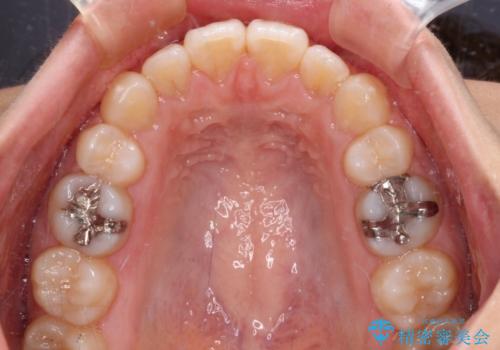

抜歯矯正の後戻り インビザライン・ライトによる矯正治療

- 矯正治療の後戻りを気にして来院された患者様です。

後戻りは軽微であったので、インビザライン・ライトにより矯正治療を行うこととしました。